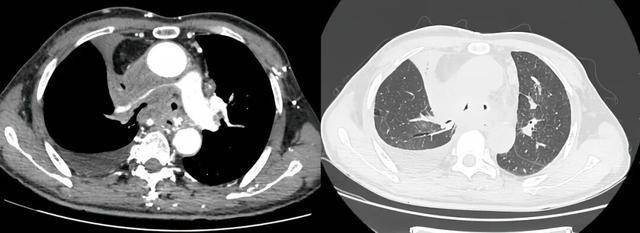

术前受压变窄的右肺动脉和中央气道

潍坊市第二人民医院完成首例气管支架、肺动脉覆膜支架同期植入术